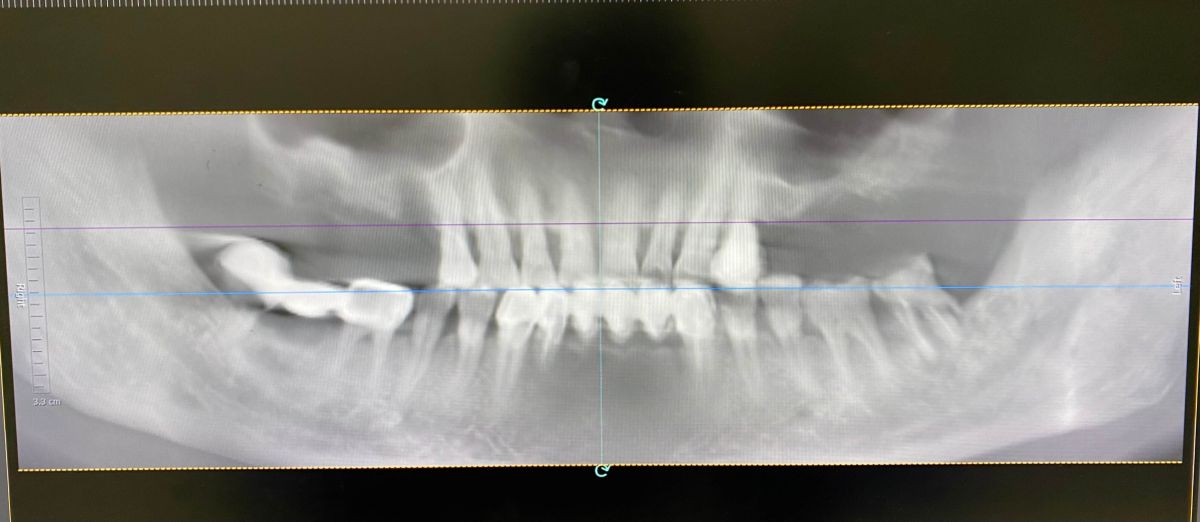

Kết quả chuẩn đoán từ phim 3D

Qua chụp CT ConeBeam 3D, bác sĩ ghi nhận chú Hòa mất toàn bộ răng hàm trên hai bên:- Mất răng R15, R16, R17 (hàm phải)

- Mất răng R25, R26, R27 (hàm trái)

- Tiêu xương nghiêm trọng

- Xoang hàm hạ thấp

- Không đủ xương để cấy Implant trực tiếp

Sau khi đánh giá tổng thể và lập kế hoạch điều trị bằng công nghệ Hansafe, bác sĩ quyết định thực hiện phác đồ như sau:- Hàm phải: Implant tại R15 – R17, phục hình 3 răng, nâng xoang kín hàm phải

- Hàm trái: Implant tại R25 – R27, phục hình 3 răng, nâng xoang hở hàm trái